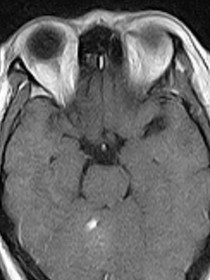

脱髓鞘是一大类病因不同,临床表现各异,但有共同病理特征的疾病。包括遗传性和获得性两大类。其特征的病理变化是神经纤维的髓鞘脱失而神经细胞相对保持完整。病因不明,可能和遗传、感染、人文地理、基因突变等因素相关。本病以儿童和青壮年多见。主要表现为肌肉无力、感觉异常、眼部症状、共济失调的反复发作。目前无有效根治措施。治疗主要目的是抑制急性期炎性脱髓鞘病变进展,避免可能的促使复发因素。晚期采取对症和支持疗法。总体来说,本病预后不佳,容易复发。